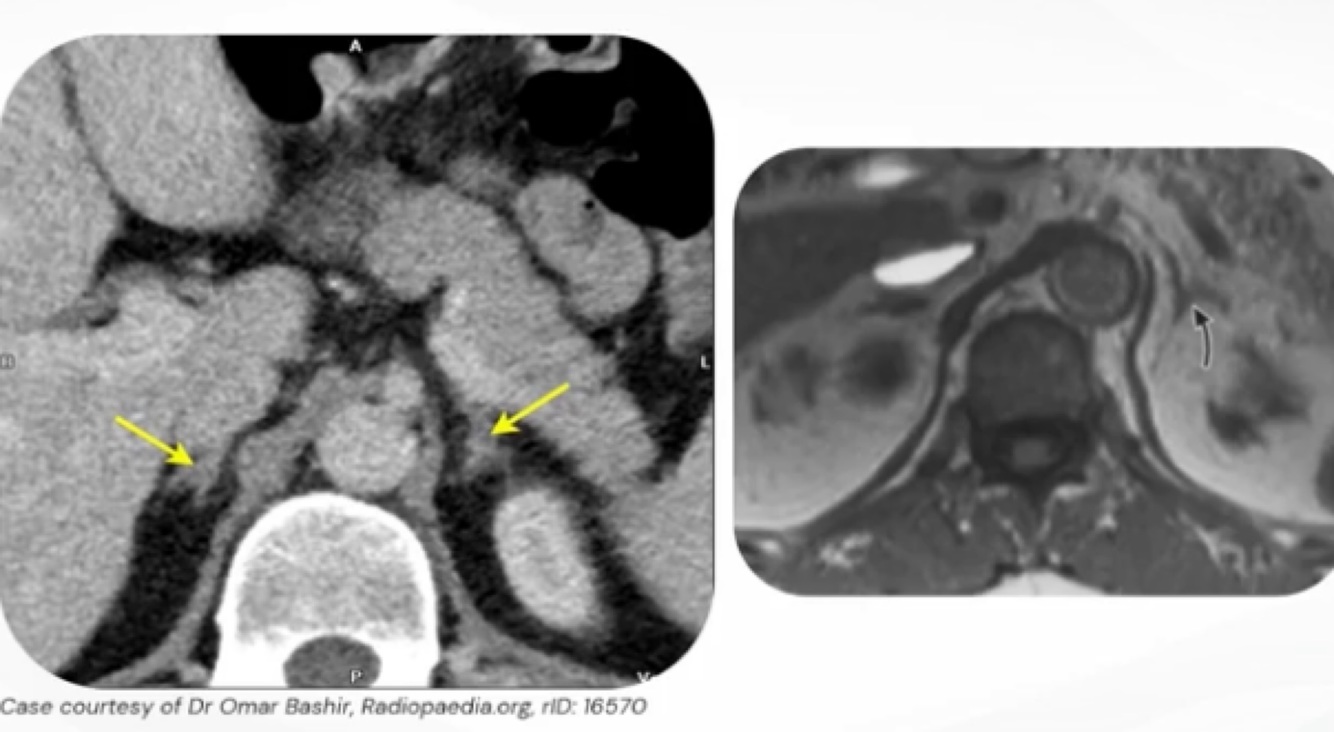

2

Q

As setas apontam para:

A

Adrenais normais.

3

Achados nas imagens:

Imagem da esquerda: adrenais normais, imagem da direita: nódulo de adrenal.